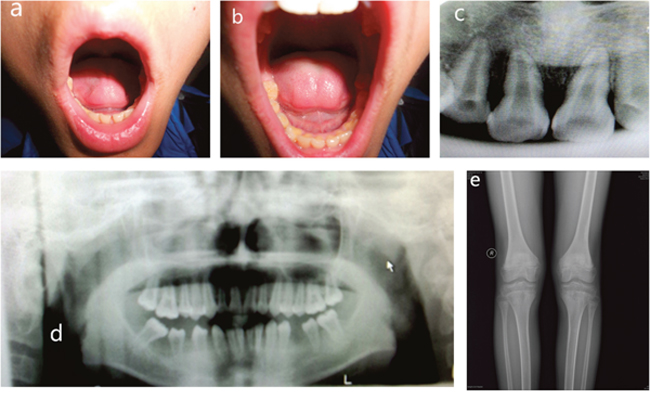

Panoramic radiographs of the proband demonstrated that the erupted teeth were normal and the radiographs of the younger brother showed reduced alveolar bone, enlarged pulp chambers, and abnormal morphology of the unerupted permanent molars. X-ray of knee joints presented metaphyseal osteoporosis changes in femurs and tibiae (Figures 2 and 3). Ultrasonographic assessment of BMD in distal radius and middle tibia showed low bone mineral density for the proband and his younger brother. In addition, their levels of serum ALP moderately decreased, whose values were 41.5 U/L and 43.4 U/L, respectively (regular scope for children 110-550 U/L). No aberrant variation in serum Ca, PTH, ESR and microelement were detected. But a high level of serum P (2.08 mmol/L and 1.97 mmol/L, respectively, normal range for children 0.90-1.34 mmol/L) and low serum 25-hydroxy vitamin D (50.40 nmol/L and 55.70 nmol/L, respectively, normal range for children 75-175mmol/L) were observed.

Figure 2: Clinical features of proband. (A, B) Intra-oral photograph of proband showing that permanent teeth were erupted. (C, D) Panoramic radiographs showing normal permanent teeth. (E) Plain films of a knee joint presenting with metaphyseal osteoporosis changes.